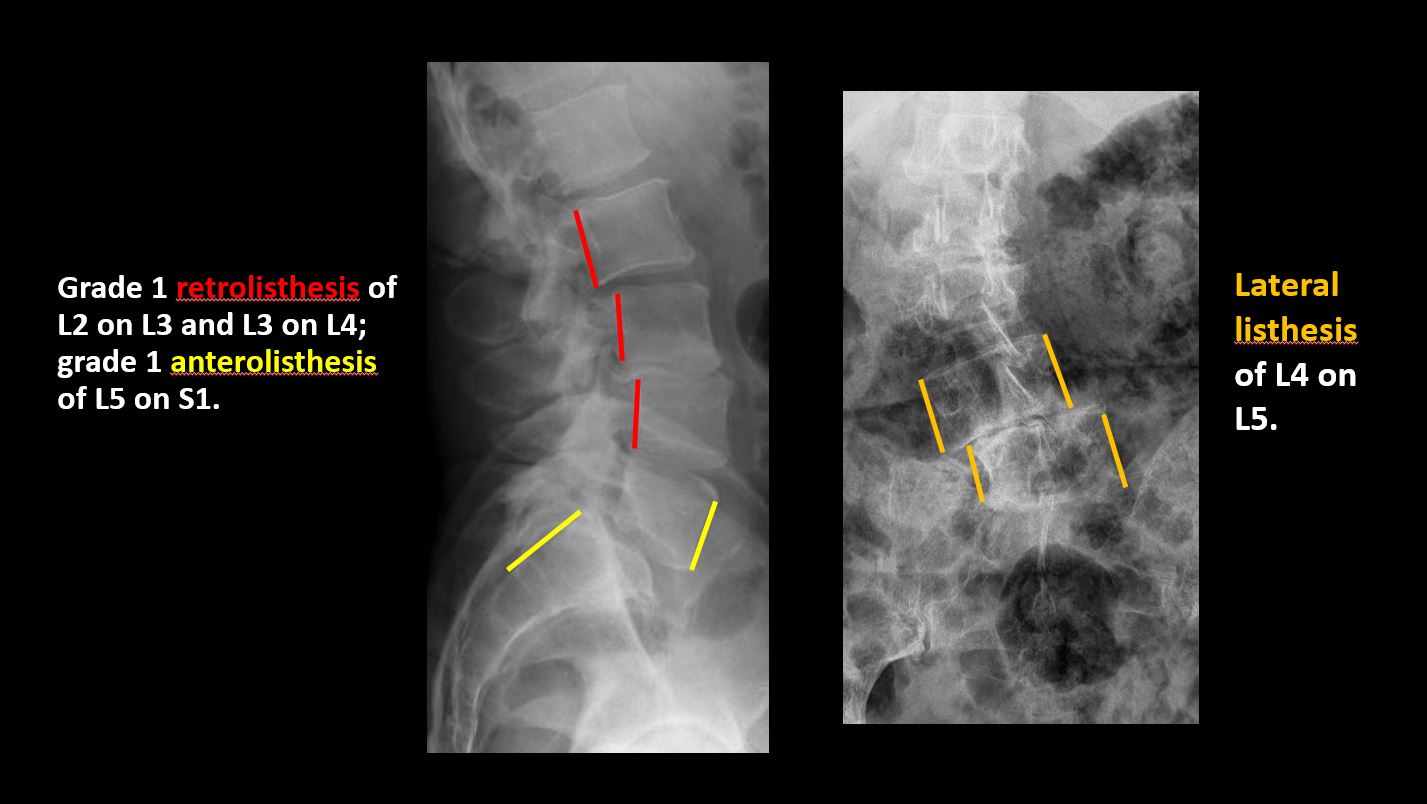

The vertebral bodies are abnormally aligned. |

The anterior and posterior vertebral body lines are abnormal or interrupted. |

There is anterior or posterior spondylolisthesis, subluxation, or rotational abnormality at a disc space. |